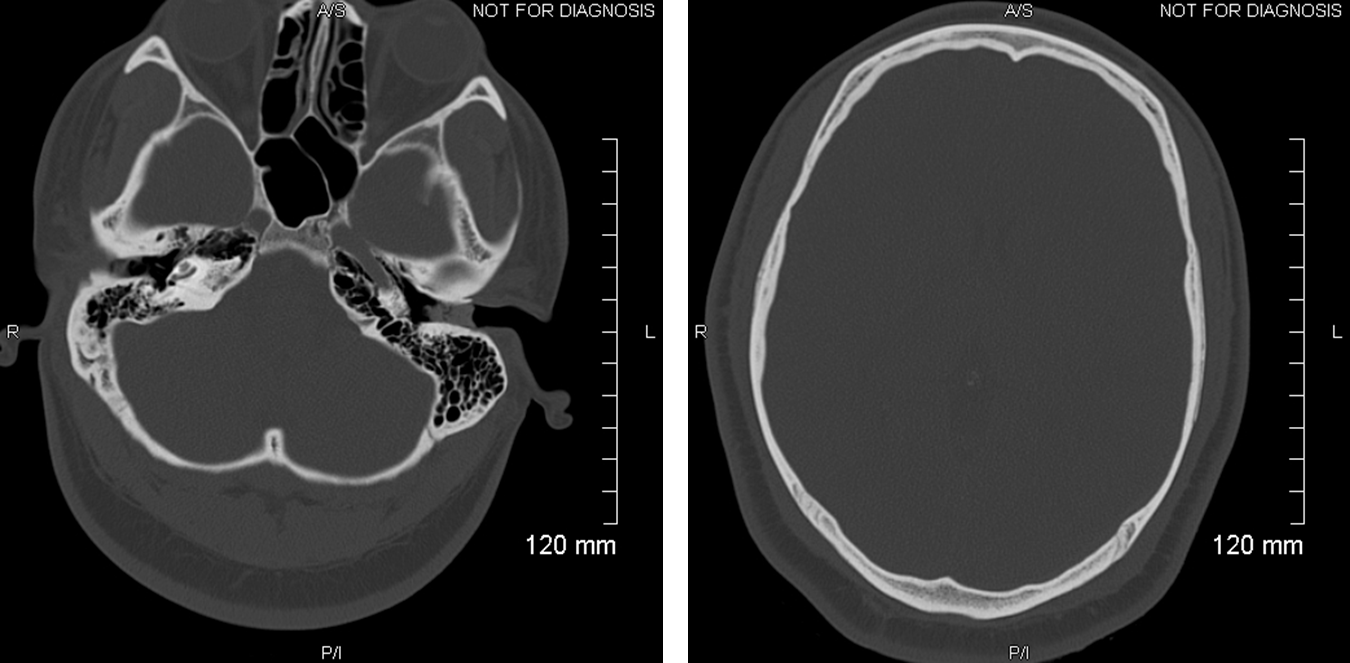

Ct Anatomy Of Brain Bone Window . Acute skull fractures are straight and are not corticated. The labeled structures are (excluding the correct side):. Atlas of the anatomy of the head and neck on a ct in axial, coronal, and sagittal sections, and 3d images. Identify the ct anatomy of the brain 3. The frontal, parietal, temporal and. Learn about the anatomy of the skull bones and sutures as seen on ct images of the brain. The bone windows should be given particular attention in the context of head injury to look for a fracture. Assessment of every brain ct requires systematic viewing of both the bone windows and the brain windows. Assess the brain and bone windows on every brain ct. Review the basics of ct imaging 2. Teaching head ct with annotated.

Normal CT head (cerebral and bone windows) Image Ct Anatomy Of Brain Bone Window Assessment of every brain ct requires systematic viewing of both the bone windows and the brain windows. Review the basics of ct imaging 2. Identify the ct anatomy of the brain 3. Acute skull fractures are straight and are not corticated. Assess the brain and bone windows on every brain ct. Teaching head ct with annotated. Learn about the anatomy. Ct Anatomy Of Brain Bone Window.

CT scan of the brain (A) soft tissue axial cuts and (B) bone window Ct Anatomy Of Brain Bone Window The bone windows should be given particular attention in the context of head injury to look for a fracture. Identify the ct anatomy of the brain 3. Assessment of every brain ct requires systematic viewing of both the bone windows and the brain windows. Review the basics of ct imaging 2. Acute skull fractures are straight and are not corticated.. Ct Anatomy Of Brain Bone Window.